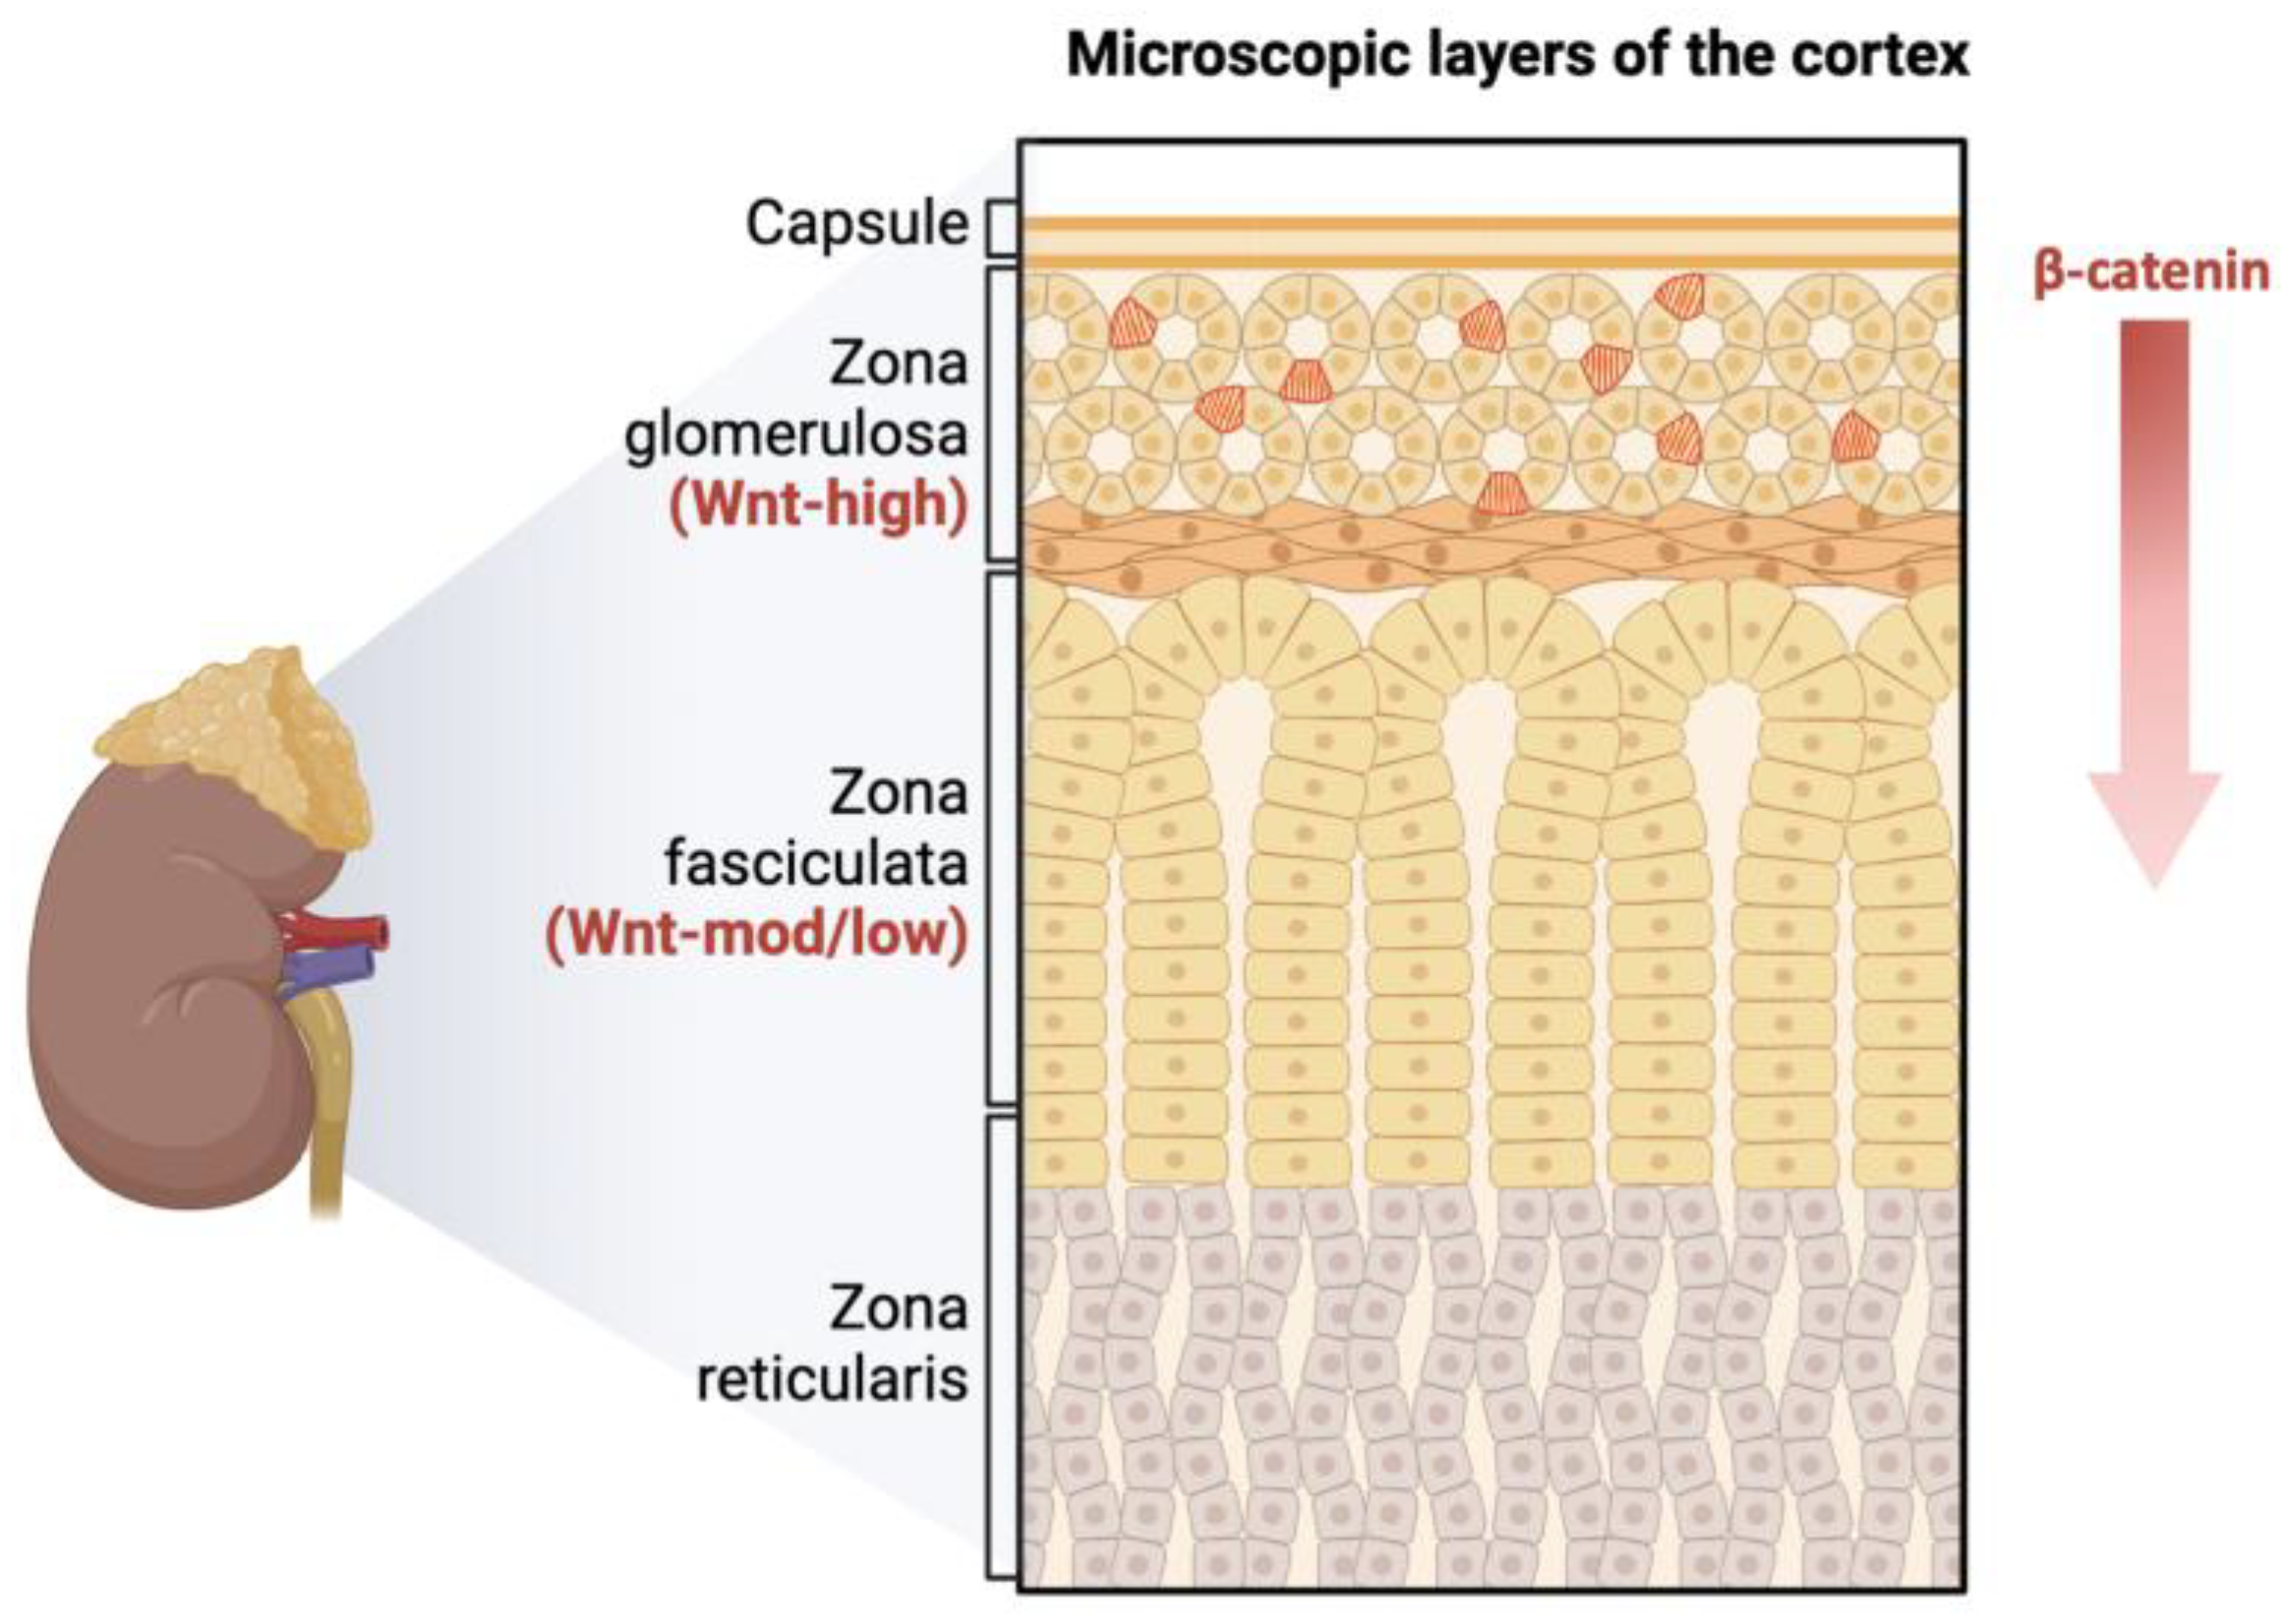

3.4. Analysis of Stem Marker Expression in Normal Adrenal Tissue

- Little, D.W.; Dumontet, T.; LaPensee, C.R.; Hammer, G.D. β-catenin in adrenal zonation and disease. Mol. Cell. Endocrinol. 2021, 522, 111120. [Google Scholar] [CrossRef]